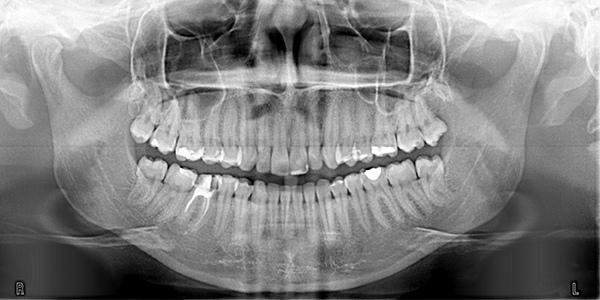

At Greenwich Braces, we offer the highest level of x-ray technology to provide the most effective care to our patients. All of our x-rays are digital, in order to ensure the least dose of radiation possible with the most accurate image. Additionally, our radiographic unit allows us to customize exposure values based on patient size, further minimizing the radiation dose. Finally, we utilize the safest radiation techniques, protecting both our patients and staff.